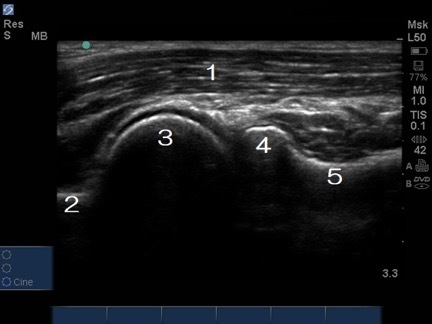

Anterior Elbow Lateral Long Axis Image

Brachialis

Radial Fossa

Capitellum

Radial Head

Radial Neck